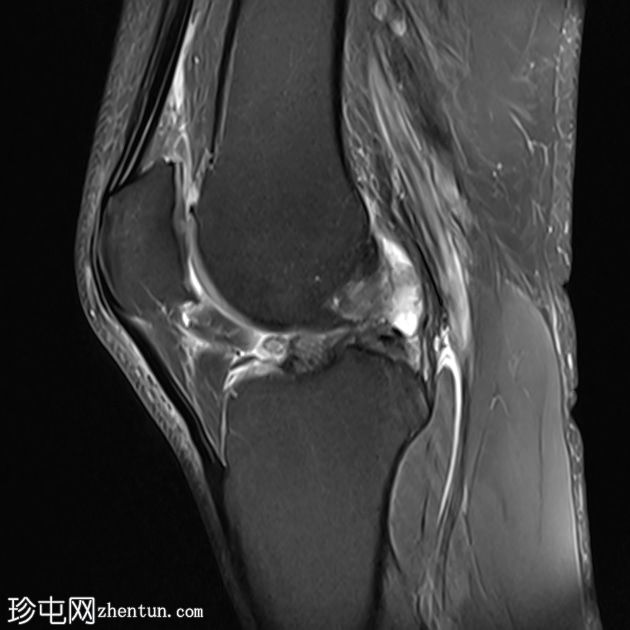

矢状面

T2和PD脂肪饱和序列上可见多处轻微高信号区,位于股四头肌腱远端、前交叉韧带、内侧副韧带近端1/3内表面深层、腘肌腱附着处。

少量膝关节积液。

其他发现包括:前交叉韧带腱鞘囊肿、膝关节后外侧轻度肌间液信号和轻度软骨软化。

印象:这些发现提示痛风性关节炎伴单钠尿酸盐晶体沉积。